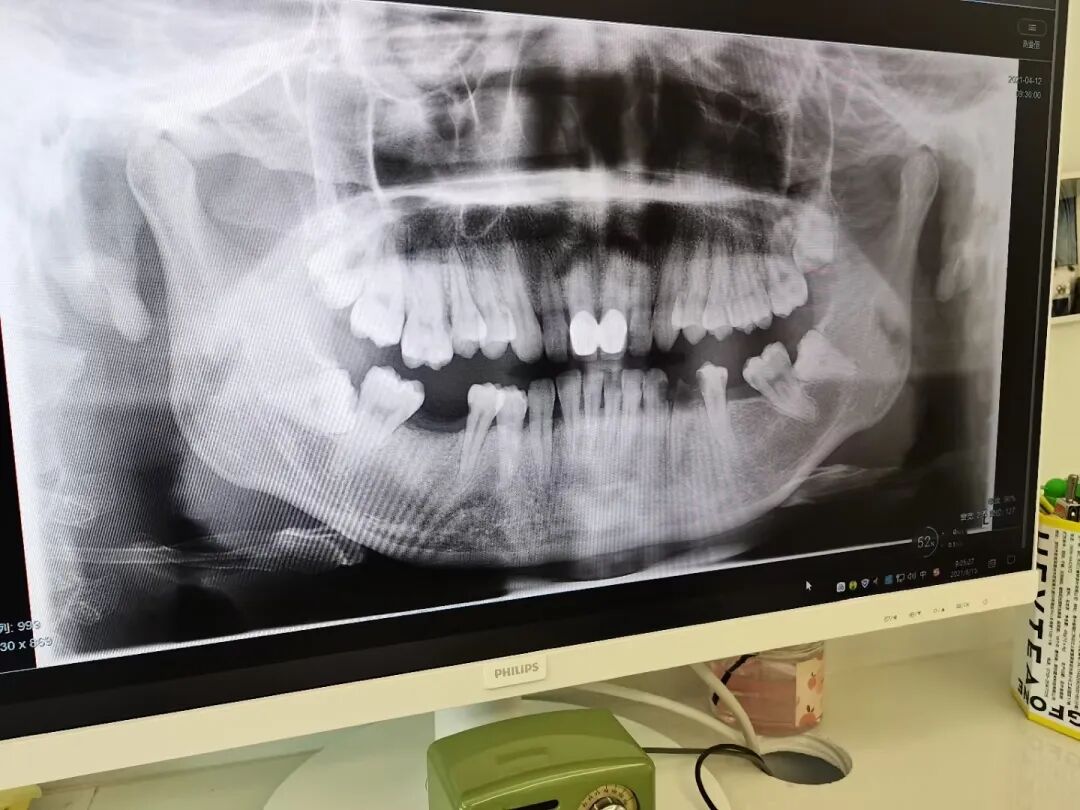

由于没有好好爱护牙齿,我的看牙经历并不好受,恐惧也让其他牙齿问题越拖越严重。偶然的机会让我开始直面牙齿问题,牙医发现有六颗龋齿要修补,门牙发黑需要处理牙套;又因为四颗智齿拔出、三个牙位缺失牙齿,旁边的牙齿倾斜,之后我要种植牙也不是件容易的事儿。

显示牙齿缺位、倾斜等问题 | 图源作者